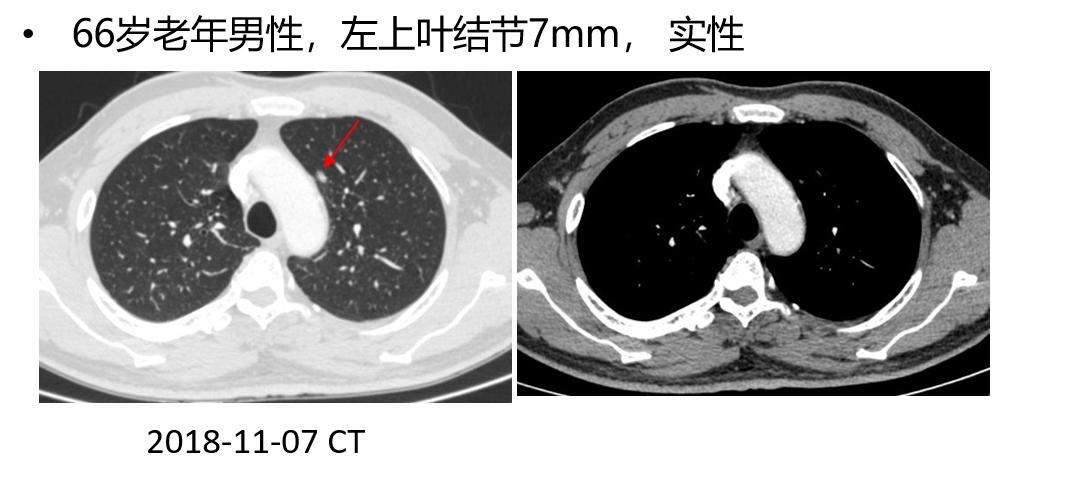

支气管镜在周围型肺癌中的应用

肺外周病变定义 PPLs were defined as lesions surrounded by pulmonary parenchyma that were endoscopically invisible(肺实质包裹内镜下不能看见) (no evidence of endobronchial lesion, extrinsic compression, submucosal tumor, narrowing, inflammation or bleeding of the bronchus)。外周的位置就是指三级及以上支气管,小于3cm为结节,大于3cm为肿块,笼统地称为肺外周病变。要注意PPL大小、位置、和支气管关系、距肋胸膜距离等。